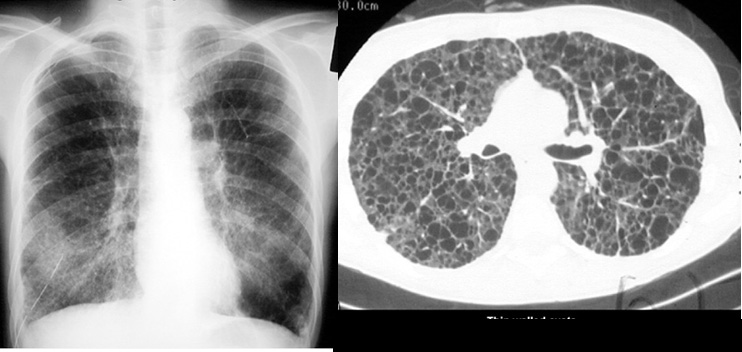

Lymphangioleiomyomatosis

Bilateral interstitial infiltrate, with a right sided chest tube inserted for chylothorax. CT showing thin walled cyts.